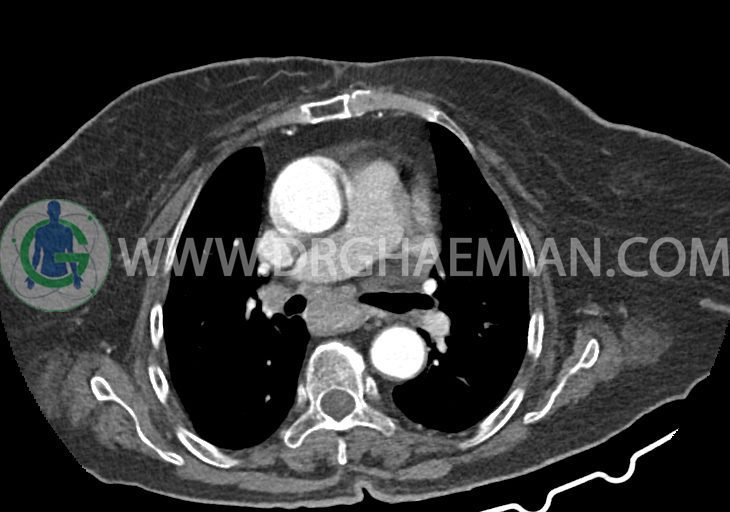

در سی تی اسکن اسپیرال ریه و مدیاستن – شکم و لگن با و بدون کنتراست خوراکی و وریدی (مولتی دیدکتور 16 با مقاطع ظریف و بازسازی های ساژیتال و کرونال):

–کاردیومگالی همراه با pericardial effusion خفیف

–یک ندول به ابعاد 19x18mm با حدود اسپیلوکه در سگمان لترال RML و دو ندول کوچکتر در مجاورت فوقانی آن به اقطار 6mm و 5mm ( مطرح کننده کارسینوم برونکوژنیک یا متاستاز )

–لنف نودهای non significant مدیاستینال با حداکثر SAD=6mm در فضای پره کارینا

–آئورت صعودی دیلاته به قطر 38mm